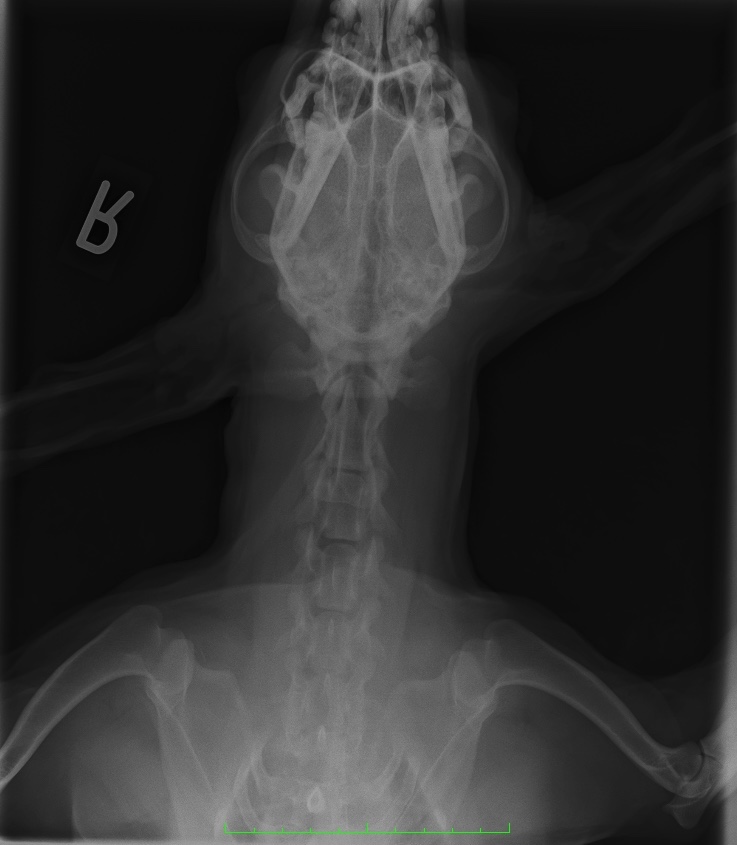

レントゲン検査

レントゲン検査は耳鏡検査などによって鼓膜や外耳道の評価ができない場合に有用な検査です。

重度の外耳炎では耳道の狭窄などにより耳鏡検査が難しいことがあります。

このような場合はレントゲン検査で外耳道の状態を評価することが可能です。

また、中耳炎が慢性化すると周囲の骨や軟部組織に変化が見られることがあります。

中耳は鼓膜の奥に位置しているため、耳鏡での観察が困難です。

そのため、中耳炎の評価にはレントゲン検査が有効ですね。